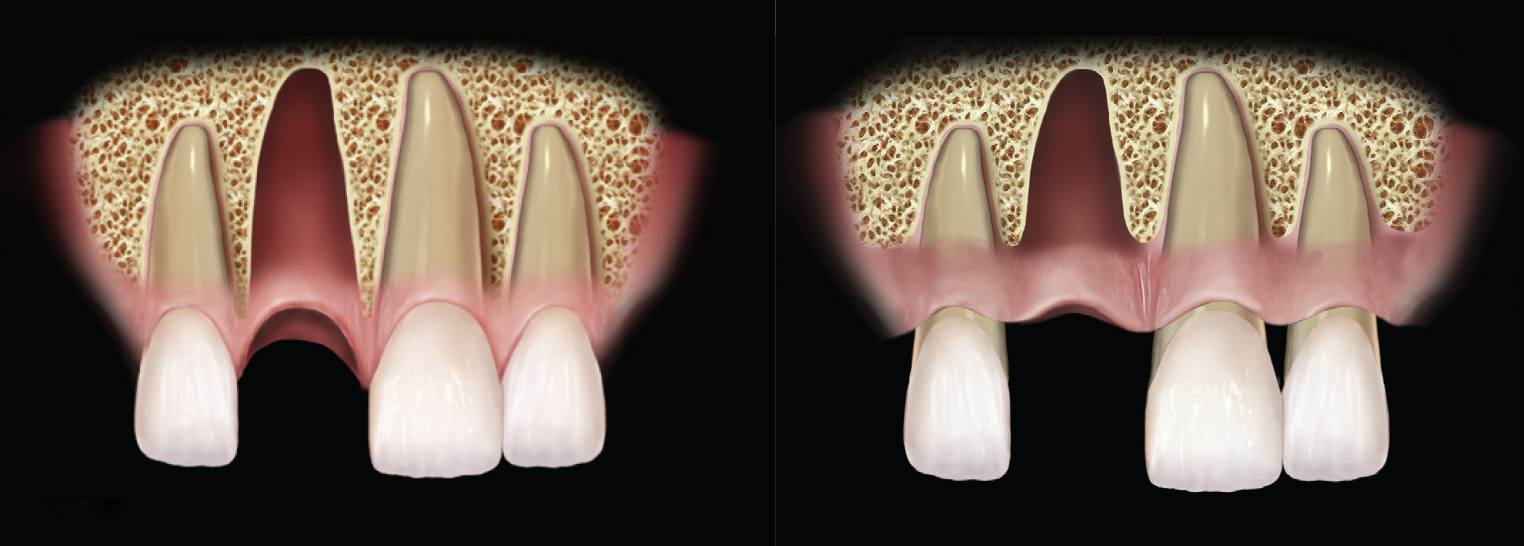

Figure 2

(Left) Example of adequate interproximal bone. The periodontium is healthy, and the bony peeks on either side of the extraction socket are aiding in supporting the interproximal papilla. (Right) A mildly reduced periodontium. Interproximal bone is present; there is enough bone to support full papilla in the embrasure spaces of the natural dentition.